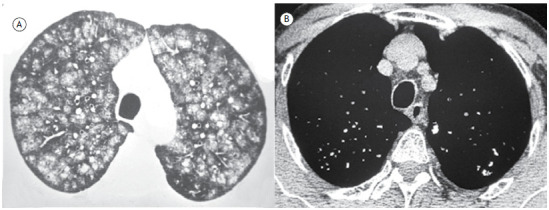

Centrilobular nodules with central calcifications.

小叶中心结节伴中央钙化。